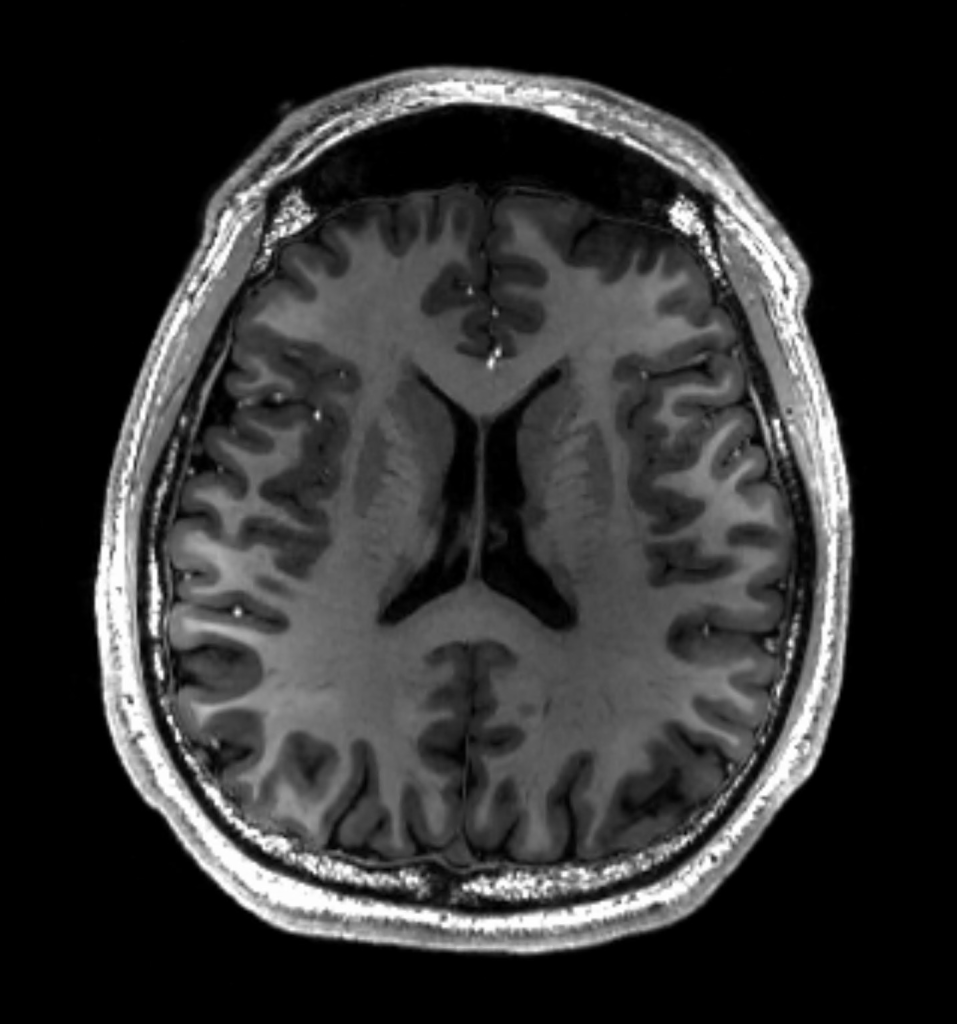

5) MRI ( Magnetic resonance imaging)

MRI Scan એ એક મેડિકલ ઈમેજીંગ technique છે કે જેમાં Radiology નો યુઝ કરી Body ની Anatomy તથા Physiology મા કોઈ પણ changes થયેલા હોય તો તેને detect કરવા માટે યુઝ થાય છે.

MRI મા srong મેગ્નેટિક ફિલ્ડ , મેગ્નેટિક ફીલ્ડ ગ્રેડિઅન્ટ અને રેડિયોવેવ્સ નો યુઝ કરી બોડી ની ઈમેજ લેવામાં આવે છે.

MRI એ મુખ્યત્વે સ્ટ્રોક, મલ્ટીપલ સ્કલેરોસીસ, ટયુમર, ટ્રોમા, હર્નિએશન, સિઝર, ને ડિટેક્ટ કરવા માટે યુઝ થાય છે.